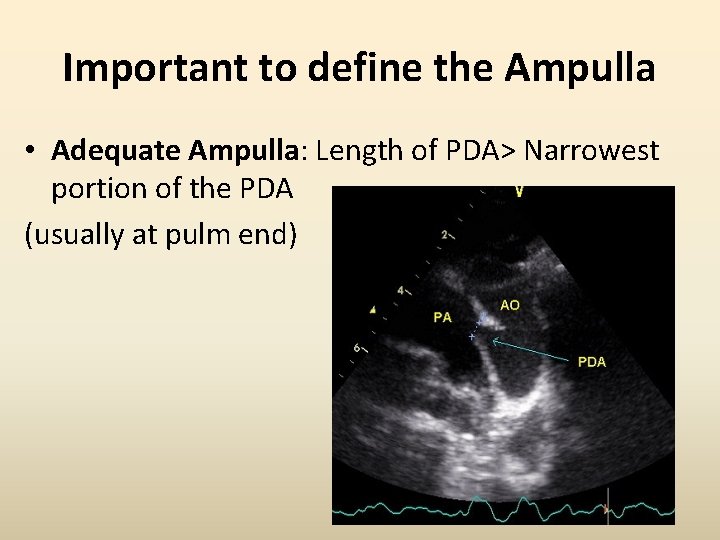

Important to define the Ampulla • Adequate Ampulla: Length of PDA> Narrowest portion of the PDA (usually at pulm end)